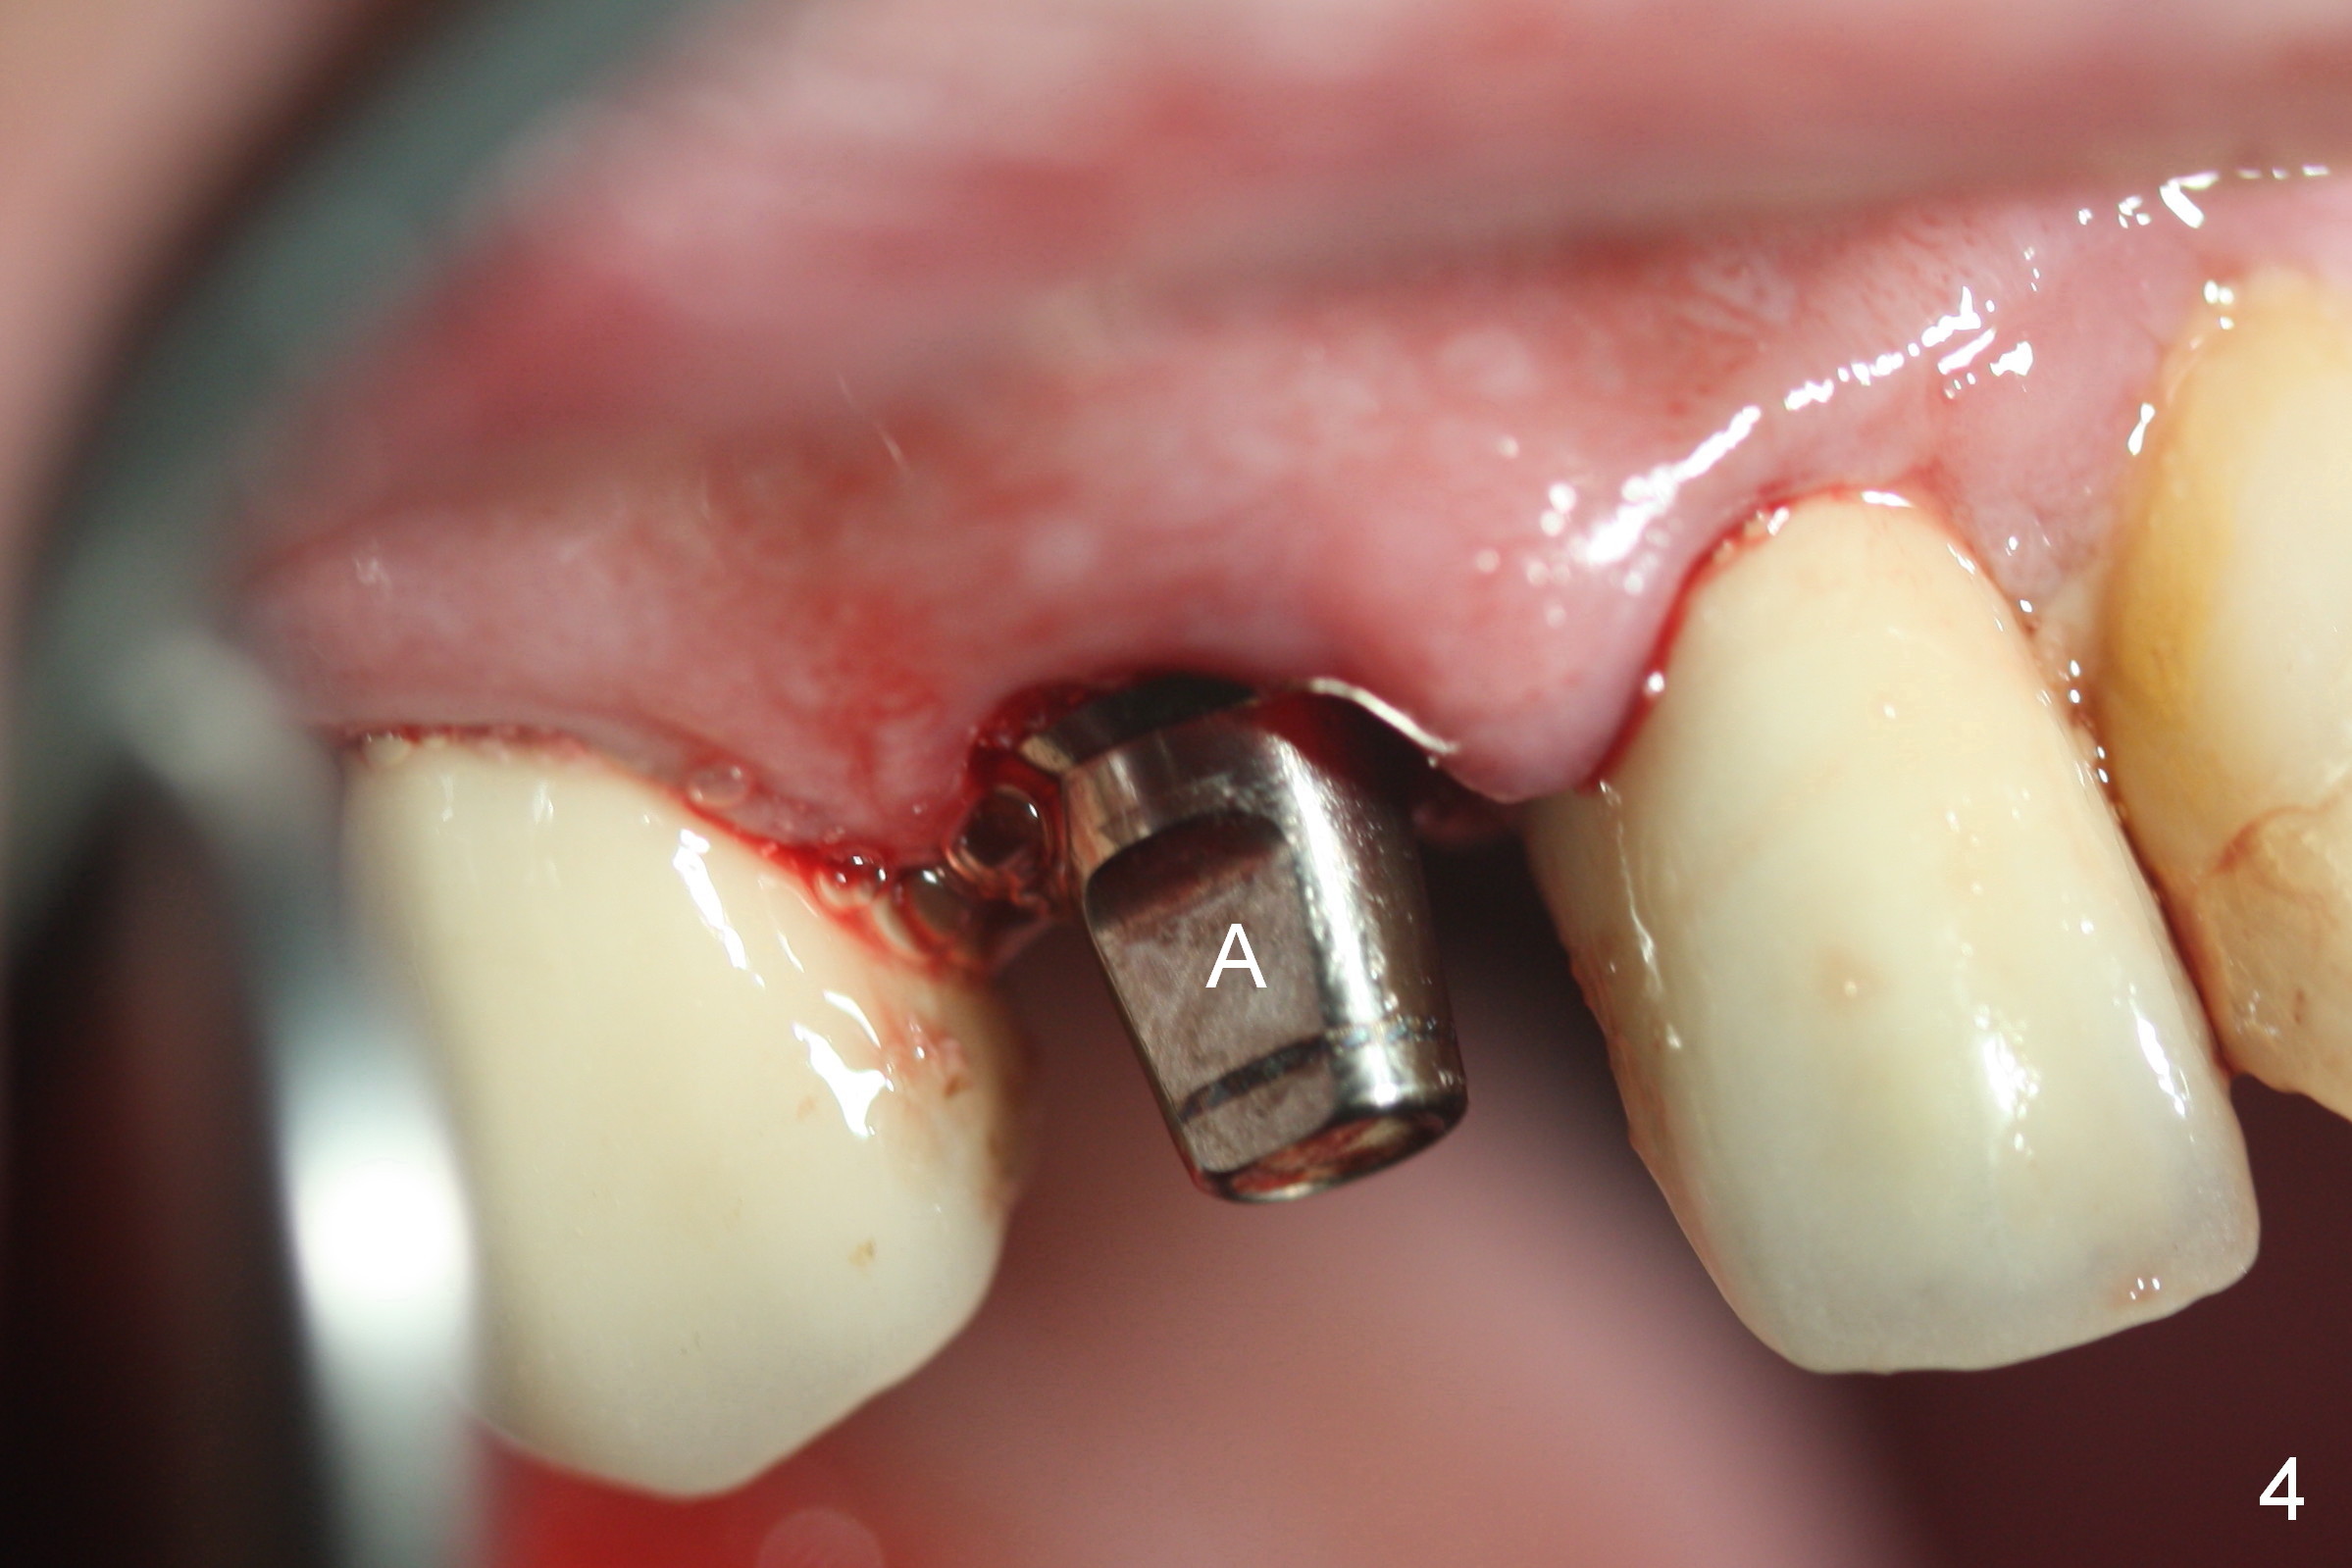

After extraction of the subgingival fractured upper right canine (Fig.1), the buccal plate is found to have been perforated at the apex. the root is measured 5x12 mm. Initial osteotomy with a 2 mm pilot drill shows that the bone is soft (Fig.2). After use of a 3.2 mm drill (underprep, normal drill size (3.7 mm)), a 4.5x15 mm implant is placed with insertion torque > 50 Ncm (Fig.3). The implant is further torqued until the implant plateau is 3 mm apical to the buccal gingival margin; a 5.5x5(3) mm abutment is placed (Fig.4,5 A). Osteogen plug is inserted into the apex of the socket, while the rest of gap is filled with mineralized cortical allograft and Osteogen. An immediate provisional (Fig.5,6 P) is fabricated to keep the graft in place, followed by periodontal dressing (Fig.6).

Three months postop, the provisional is dislodged (Fig.7-9). The mesial gingiva is hypertrophic buccally (Fig.8 *) and lingually (Fig.9 *). There appears to biologic width violation (Fig.5). The abutment should be changed to the one with smaller in diameter and longer in cuff (4.5x5(4) mm) with the buccal margin reduction.